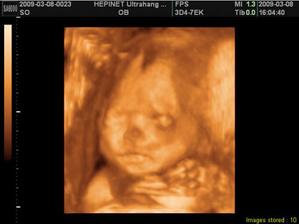

Naša bambuľka Nela

Tak už som tu. Ponáhľala som sa na svet, ale na poslednú chvíľu som si to rozmyslela, tak museli maminke robiť sekciu. Bráško ma dostal ako "darček" za vysvedčko. Neviem, či je z toho na mäkko, ale asi ma ľúbi, keď ma stále bozkáva.....veď si na seba čoskoro zvykneme.